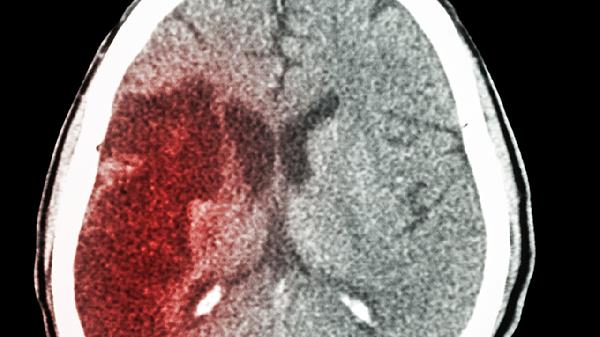

5、中风后遗症康复期

用于脑梗塞或脑出血恢复期的烦躁不安、语言不利等后遗症状辅助治疗。这类患者多见肢体麻木僵硬伴随情绪抑郁,通常与脑组织缺血缺氧有关。康复期用药需配合脑心通胶囊、银杏叶片等活血化瘀药物,但新发脑梗急性期禁用。康复训练应遵循循序渐进原则,避免过度疲劳。